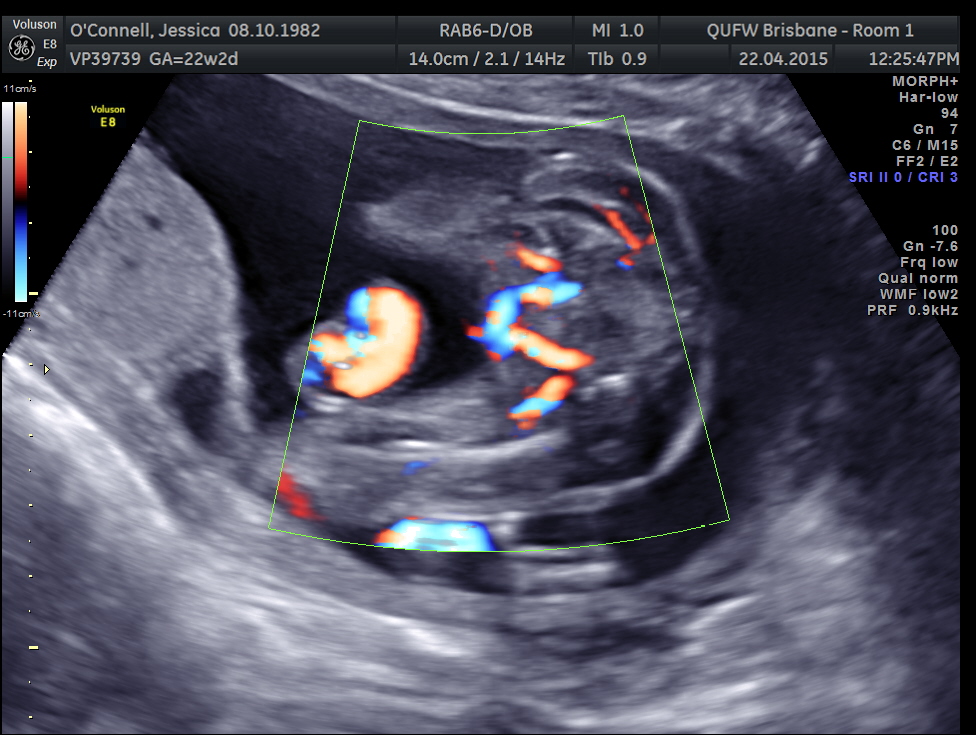

Attachment 24888Attachment 24889

2 more images. This is all I have

Girl lean